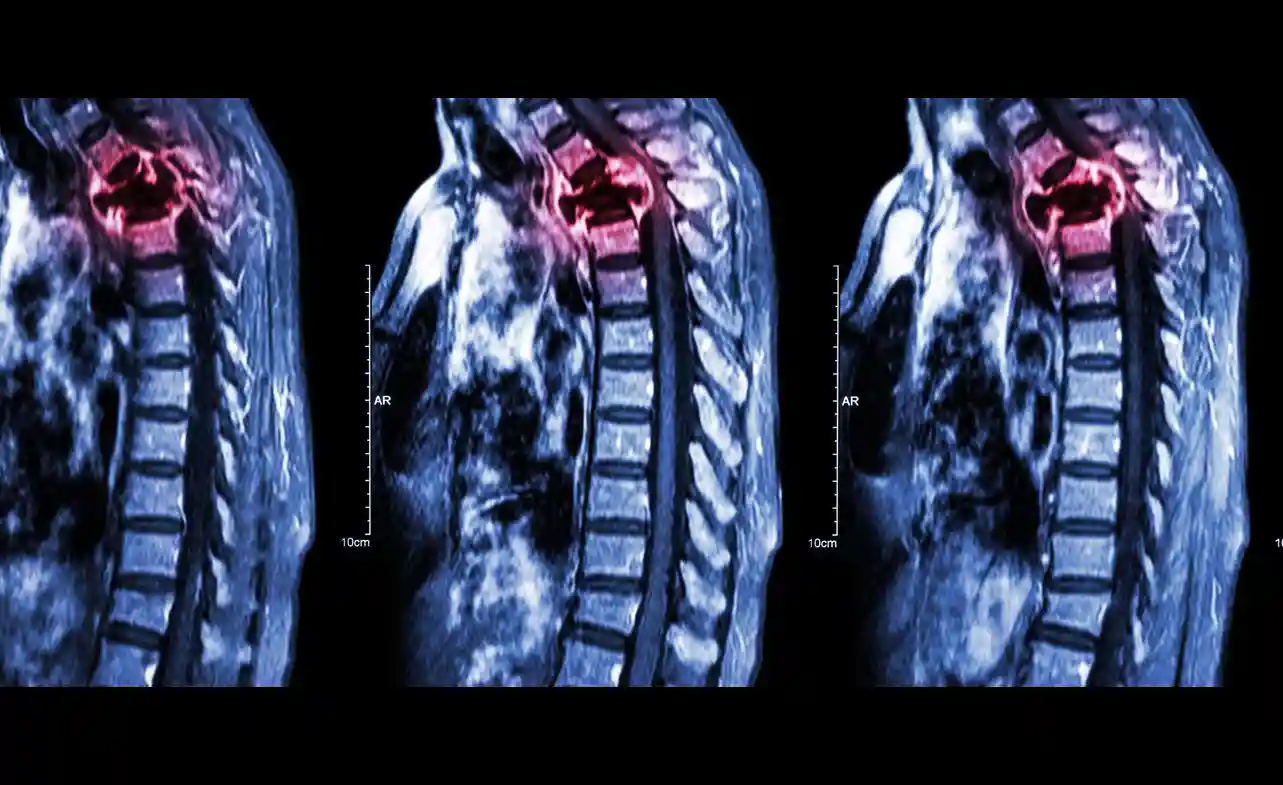

Diagnostic Approaches for Lung Cancer Spread to Bone

Diagnosing bone metastasis is crucial for identifying lung cancer that has spread to the bones and determining life expectancy. Imaging tests are among the diagnostic methods commonly used to detect bone metastasis, including:

Imaging Test Description

X-ray A basic imaging test that can identify bone abnormalities and check for bone fractures or osteoporosis. However, it may not always detect early-stage bone metastasis.

CT Scan A more detailed imaging test that combines X-rays with computer technology to produce a more comprehensive view of the bones. It can identify bone destruction and see abnormal tissue growth.

Bone Scan A nuclear medicine imaging test that uses small amounts of radioactive material to identify areas of active bone metabolism. It can detect early bone metastasis and is highly sensitive, but may not be specific in identifying cancer cells.

Aside from imaging, other diagnostic approaches may involve blood tests, biopsy, and other methods that evaluate the spread of cancer. Consulting with a medical expert is essential to determine the best diagnostic approach for individual cases.